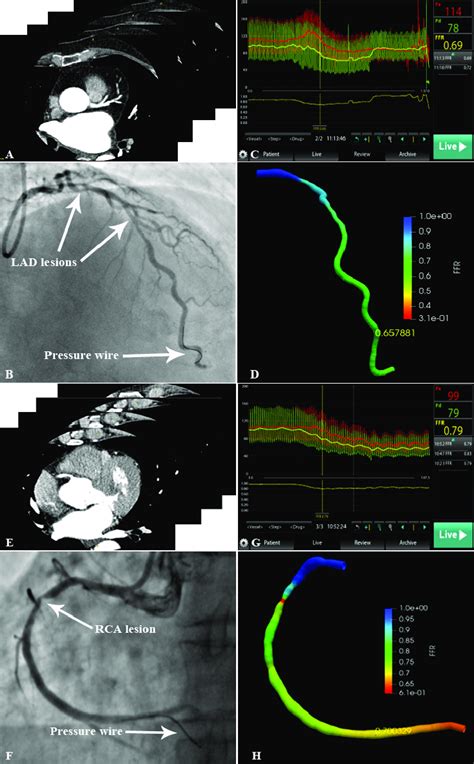

So, you’re probably wondering, “How on earth do they measure this FFR thing?” Great question! The process of measuring Fractional Flow Reserve (FFR) , especially in the Left Anterior Descending (LAD) artery , is a pretty sophisticated procedure, usually done during a cardiac catheterization (also known as an angiogram). It’s not something done out of the blue; it’s typically performed when an angiogram shows a significant-looking blockage in a coronary artery, and the cardiology team needs to determine its functional significance. Here’s the lowdown on how it’s done, guys. First off, the patient is prepped for a standard cardiac catheterization. A thin, flexible tube called a catheter is inserted into an artery, usually in the wrist or groin, and guided up to the heart. Once the cardiologist can visualize the coronary arteries using X-ray and contrast dye, they’ll assess the blockage in the LAD. Now, for the FFR part: a special pressure wire is advanced through the catheter and carefully threaded past the stenosis (the narrowing) in the LAD. This wire has tiny sensors on its tip that can measure pressure. To get an accurate FFR reading, the heart needs to be under maximal blood flow conditions . This is usually achieved by administering a medication, either intravenously or directly into the coronary artery, that causes the blood vessels to dilate (widen) significantly. This medication, often adenosine or a similar vasodilator, simulates the conditions of intense physical exertion or stress. Once maximal hyperemia (high blood flow) is achieved, the pressure sensor on the wire measures the pressure distal to the blockage (further down the artery). Simultaneously, another pressure sensor, either on the catheter itself or a sensor wire left in the aorta, measures the pressure in the aorta. The FFR value is then calculated as the ratio of the distal coronary pressure to the aortic pressure. An FFR value of 1.0 would mean no pressure drop, indicating no significant functional blockage. An FFR value below 0.80 (meaning the pressure beyond the blockage is less than 80% of the pressure before it) generally indicates a physiologically significant stenosis that is likely limiting blood flow to the heart muscle and may warrant treatment. The whole procedure is performed by highly skilled interventional cardiologists, and it provides invaluable objective data to guide treatment decisions, helping to avoid unnecessary interventions and ensure timely treatment for those who will benefit most. It’s a testament to how far cardiac imaging and physiology have come!

Alright, so the FFR measurement has been taken for that Left Anterior Descending (LAD) artery . Now comes the critical part: interpreting those numbers. This is where the magic happens, guys, and where objective data truly guides patient care. The Fractional Flow Reserve (FFR) value is a simple ratio, but its implications are profound. Remember, it’s calculated by comparing the pressure after the blockage in the LAD to the pressure before it (or in the aorta) when the heart is pumping at maximum capacity (hyperemic state). So, what do these numbers tell us?

FFR = 1.0 : This is the ideal scenario. An FFR of 1.0 means there’s no pressure drop across the lesion. In simple terms, the blockage, even if it looks noticeable on an angiogram, isn’t actually hindering blood flow significantly. The heart muscle downstream is getting all the oxygenated blood it needs, even during peak demand. In this case, intervention like stenting is usually not recommended for this specific lesion.

FFR > 0.80 (but < 1.0) : If the FFR is, say, 0.90 or 0.85, it means there’s a slight pressure drop, but it’s generally considered to be below the threshold of causing significant ischemia (lack of oxygen) to the heart muscle. While there might be some minor impediment, it’s often not severe enough to warrant immediate invasive treatment. The decision here might involve close monitoring, medical management, and lifestyle changes.

FFR ≤ 0.80 : This is the threshold that typically signals a physiologically significant stenosis. An FFR of 0.80 or lower (like 0.75, 0.70, or even less) indicates that the blockage is causing a substantial reduction in blood flow to the heart muscle. When the heart needs more oxygen – during exercise, stress, or even just at rest if the blockage is severe – this reduced flow can lead to symptoms like chest pain (angina), shortness of breath, or even a heart attack. When FFR is in this range, especially in the critical LAD artery, it strongly suggests that the patient would benefit from revascularization – procedures like angioplasty with stenting or coronary artery bypass surgery to restore adequate blood flow.

It’s important to remember that while 0.80 is the widely accepted threshold, clinical decisions are always made in the context of the individual patient’s symptoms, other medical conditions, and the overall picture. However, the FFR result provides a powerful, objective piece of evidence that helps cardiologists move beyond just the visual appearance of a blockage to understand its real-world impact on heart function. This data-driven approach is what makes FFR such a game-changer in modern cardiology, ensuring that patients receive the most appropriate and effective care for their specific situation.